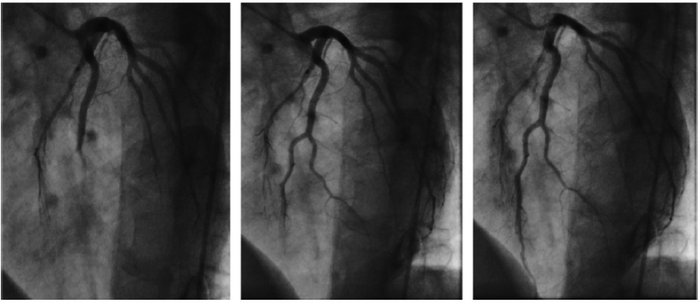

A síndrome coronariana aguda pode se apresentar de diversas e variáveis formas, dentre as quais a controversa síndrome Y…

A síndrome X cardíaca constitui uma entidade clínica semelhante a angina do peito, onde há isquemia miocárdica, porém com coronárias…